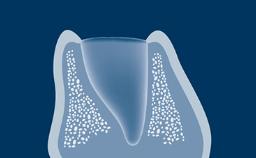

Quando um dente é extraído, o osso alveolar que suporta o dente é reabsorvido ao longo do tempo. Essa reabsorção resulta em uma redução no volume ósseo alveolar, como mostrado neste exemplo clínico de um incisivo central superior direito ausente. O osso diminuiu significativamente na largura orofacial, e isso está em conflito com o requisito fundamental da implantodontia de que os implantes são instalados na posição correta determinada pela prótese dentária. Quando o osso alveolar é reabsorvido, muitas vezes é necessário aumentá-lo para garantir que os implantes possam ser instalados corretamente e completamente incorporados ao osso. Este módulo descreverá uma técnica específica para aumento ósseo conhecida como regeneração óssea guiada ou ROG.